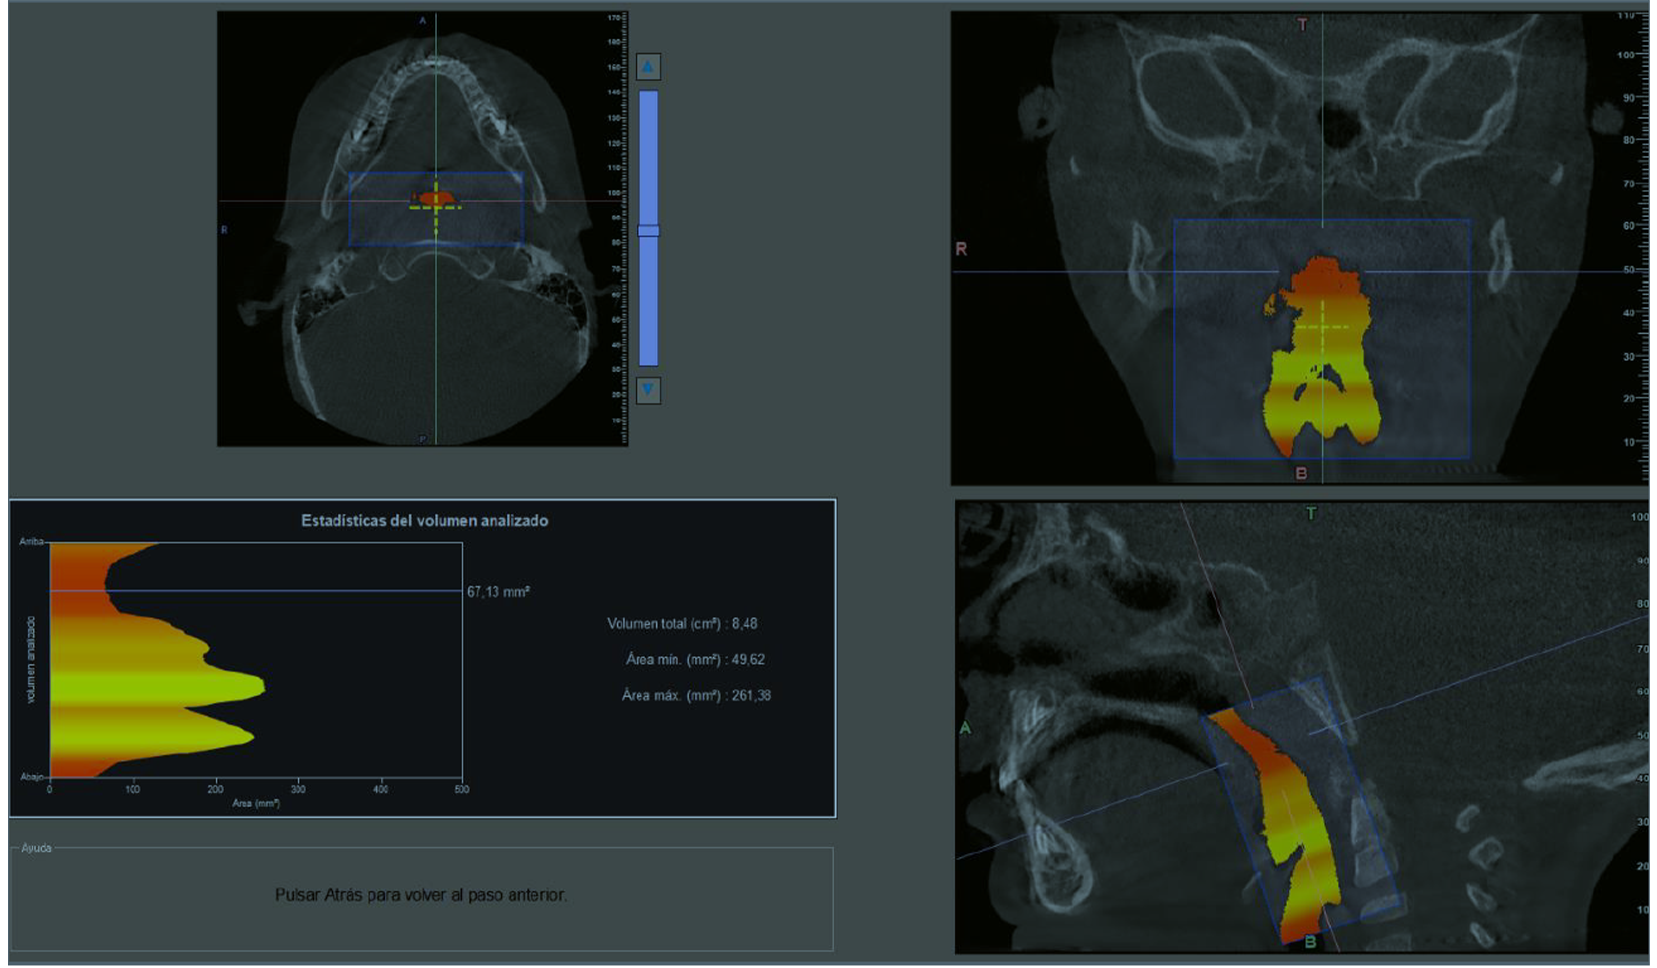

Via Aérea (Sahos-Roncopatía)